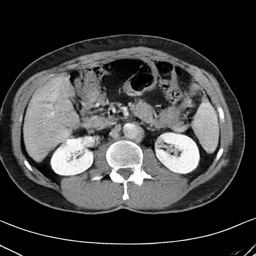

In many clinical settings, the use of both Computed Tomography (CT) and Magnetic Resonance (MRI) is necessary to pursue a thorough understanding of the patient's anatomy and to plan a suitable therapeutical strategy; this is often the case in MRI-based radiotherapy, where CT is always necessary to prepare the dose delivery, as it provides the essential information about the radiation absorption properties of the tissues. Sometimes, MRI is preferred to contour the target volumes. However, this approach is often not the most efficient, as it is more expensive, time-consuming and, most importantly, stressful for the patients. To overcome this issue, in this work, we analyse the capabilities of different configurations of Deep Learning models to generate synthetic CT scans from MRI, leveraging the power of Generative Adversarial Networks (GANs) and, in particular, the CycleGAN architecture, capable of working in an unsupervised manner and without paired images, which were not available. Several CycleGAN models were trained unsupervised to generate CT scans from different MRI modalities with and without contrast agents. To overcome the problem of not having a ground truth, distribution-based metrics were used to assess the model's performance quantitatively, together with a qualitative evaluation where physicians were asked to differentiate between real and synthetic images to understand how realistic the generated images were. The results show how, depending on the input modalities, the models can have very different performances; however, models with the best quantitative results, according to the distribution-based metrics used, can generate very difficult images to distinguish from the real ones, even for physicians, demonstrating the approach's potential.